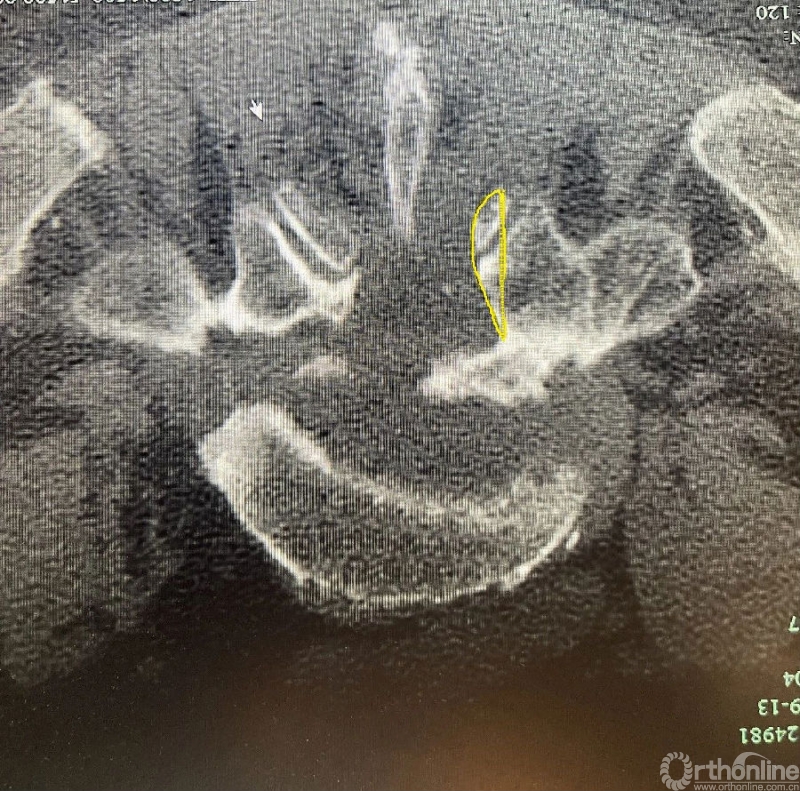

脊柱外科医生常常在术后进行减压程度的评估,以期望神经根的充分减压,而不是侧隐窝的减压不彻底。

充分减压

减压不彻底

30度镜子有更广的视野,但是在减压的时候,在没有充分对corner部位减压的情况下,可能通过旋转30度镜子即可清楚的看到神经根及椎弓根内壁。

但这也可能误导临床医生掌握一个错误的减压外界,进而过早的结束手术。

0度镜子则不存在这种情况。其手术视野与开放手术视野一样,不存在视野的偏差,corner部位对神经根的遮挡可全部看到并在其监视下完成减压。

当我们用30度镜子看到减压范围足够的时候,使用0度镜子观察可能减压范围并不足够。这并不是说30度的镜子不能做到充分减压,可能需要掌握一定技巧和经验以便用30度镜子完成充分减压。